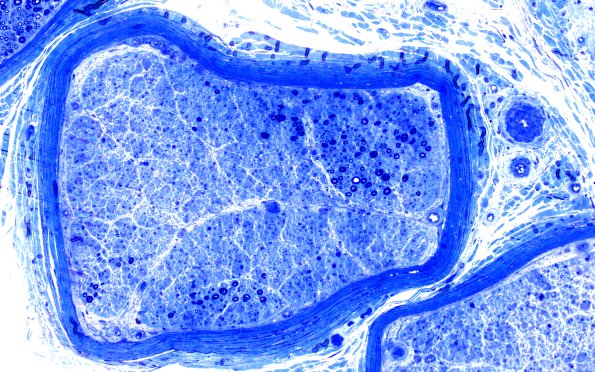

2E5 (Case 2) Block B1 20X

Intrafascicular variation in axon density. (Plastic sections)